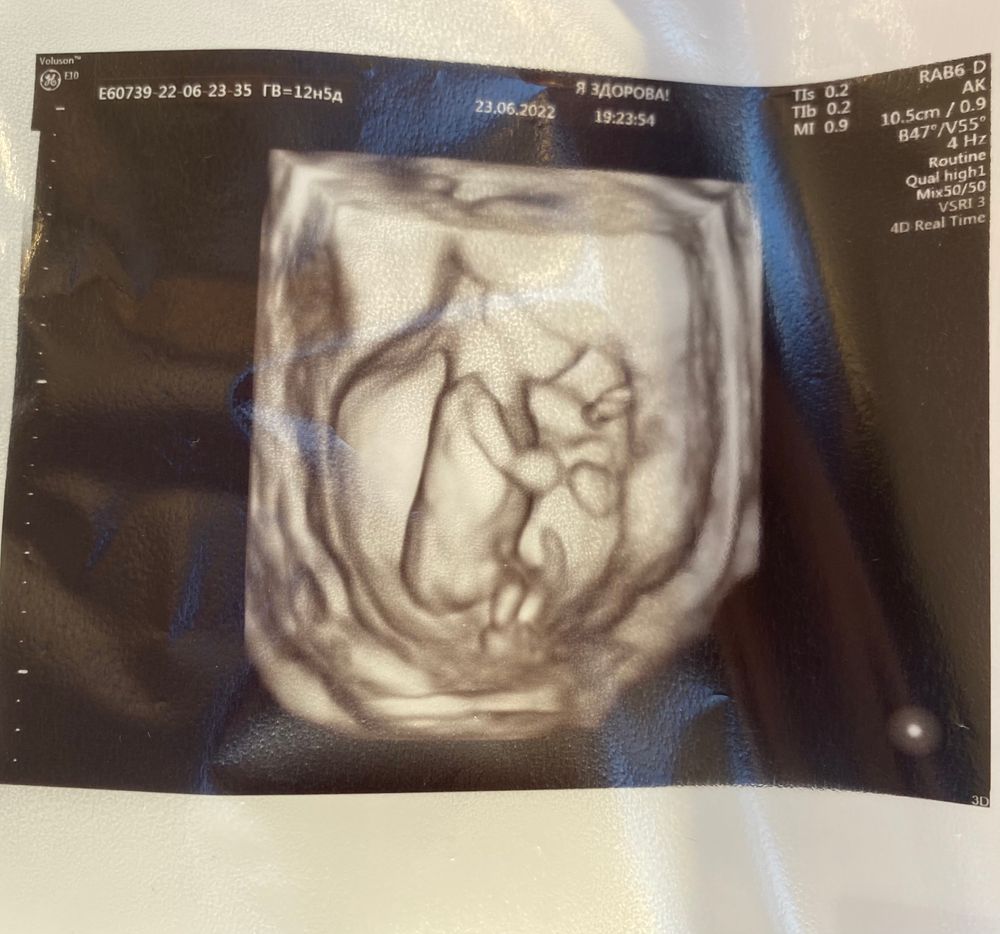

2. У нас на 99,9% будет девочка ,муж там от счастья чуть с ума не пошёл ,сразу вылетел из кабинета звонить родителям и лучшему другу с криком «У меня будет дочь»)))

Мы немножко опережаем по графику роста , носовая кость и все что положено в наличии.Результаты и фото прикладываю ниже.

в конце малышка нам помахала ручкой )Наталья Сергеевна даже перемотала этот момент и помахала ей в ответ со словами «Пока-пока»)Это было безумно мило.Единственное советовала аккуратнее с интимной жизнью .все остальное в норме ,опережаем примерно на 4-5 дней ,а на 7-8 неделях наоборот не догоняли до срока )Теперь мы крупненькие,выросли ,с ручками и ножками ,все хорошо ,машем на прощание маме с папой )